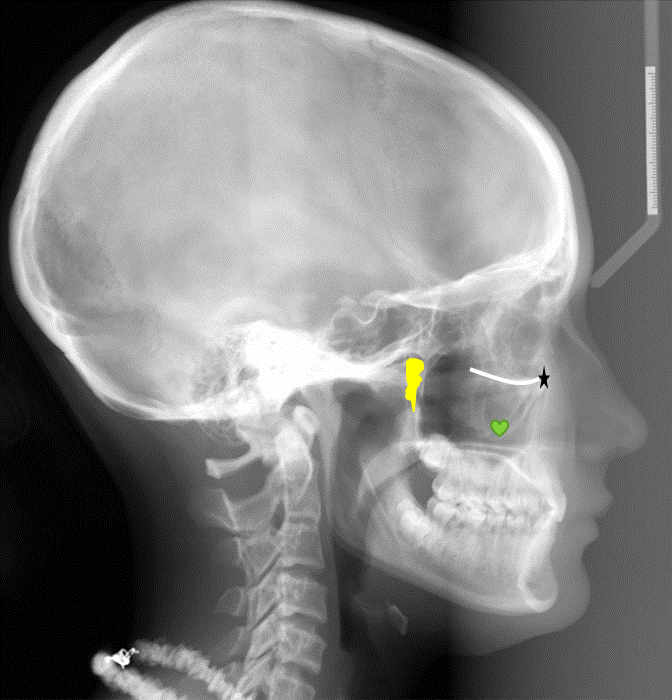

Baby Neck Xray. The vertebrae (neck bones) the. These are the 7 bones of the spine in the neck.

From The Side (Lateral View) To View The Soft Tissues Of The Neck.

This site has been made in order to have a quick “reference” look at normal pediatric bone xrays from the ages of day 1 up to 15 years. The vertebrae (neck bones) the. The normal cervical spine in infants and children.

Lateral Normal Appearances Of The Soft Tissues Of The Neck.

Cyst in cystic lesions the diagnosis can frequently be made. From the side (lateral view) to view the soft tissues of the neck; These are the 7 bones of the spine in the neck.